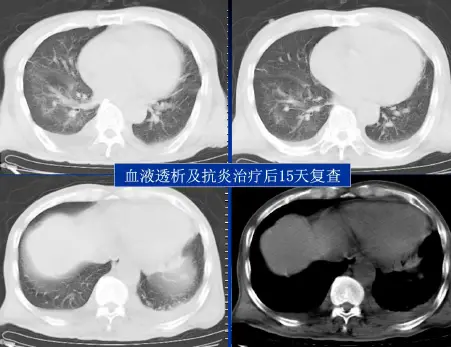

病例:男,33岁,急性肾衰肺水肿。CT表现:①肺间质性肺水肿:两肺血管束增多、增粗,边缘模糊;②肺泡性肺水肿:两肺透光度减低,并见广泛性分布结节样、斑片样密度增高影及毛玻璃样影,边缘模糊,以两肺内、中带分布较明显,形成典型“蝶翼征”;③胸腔积液。